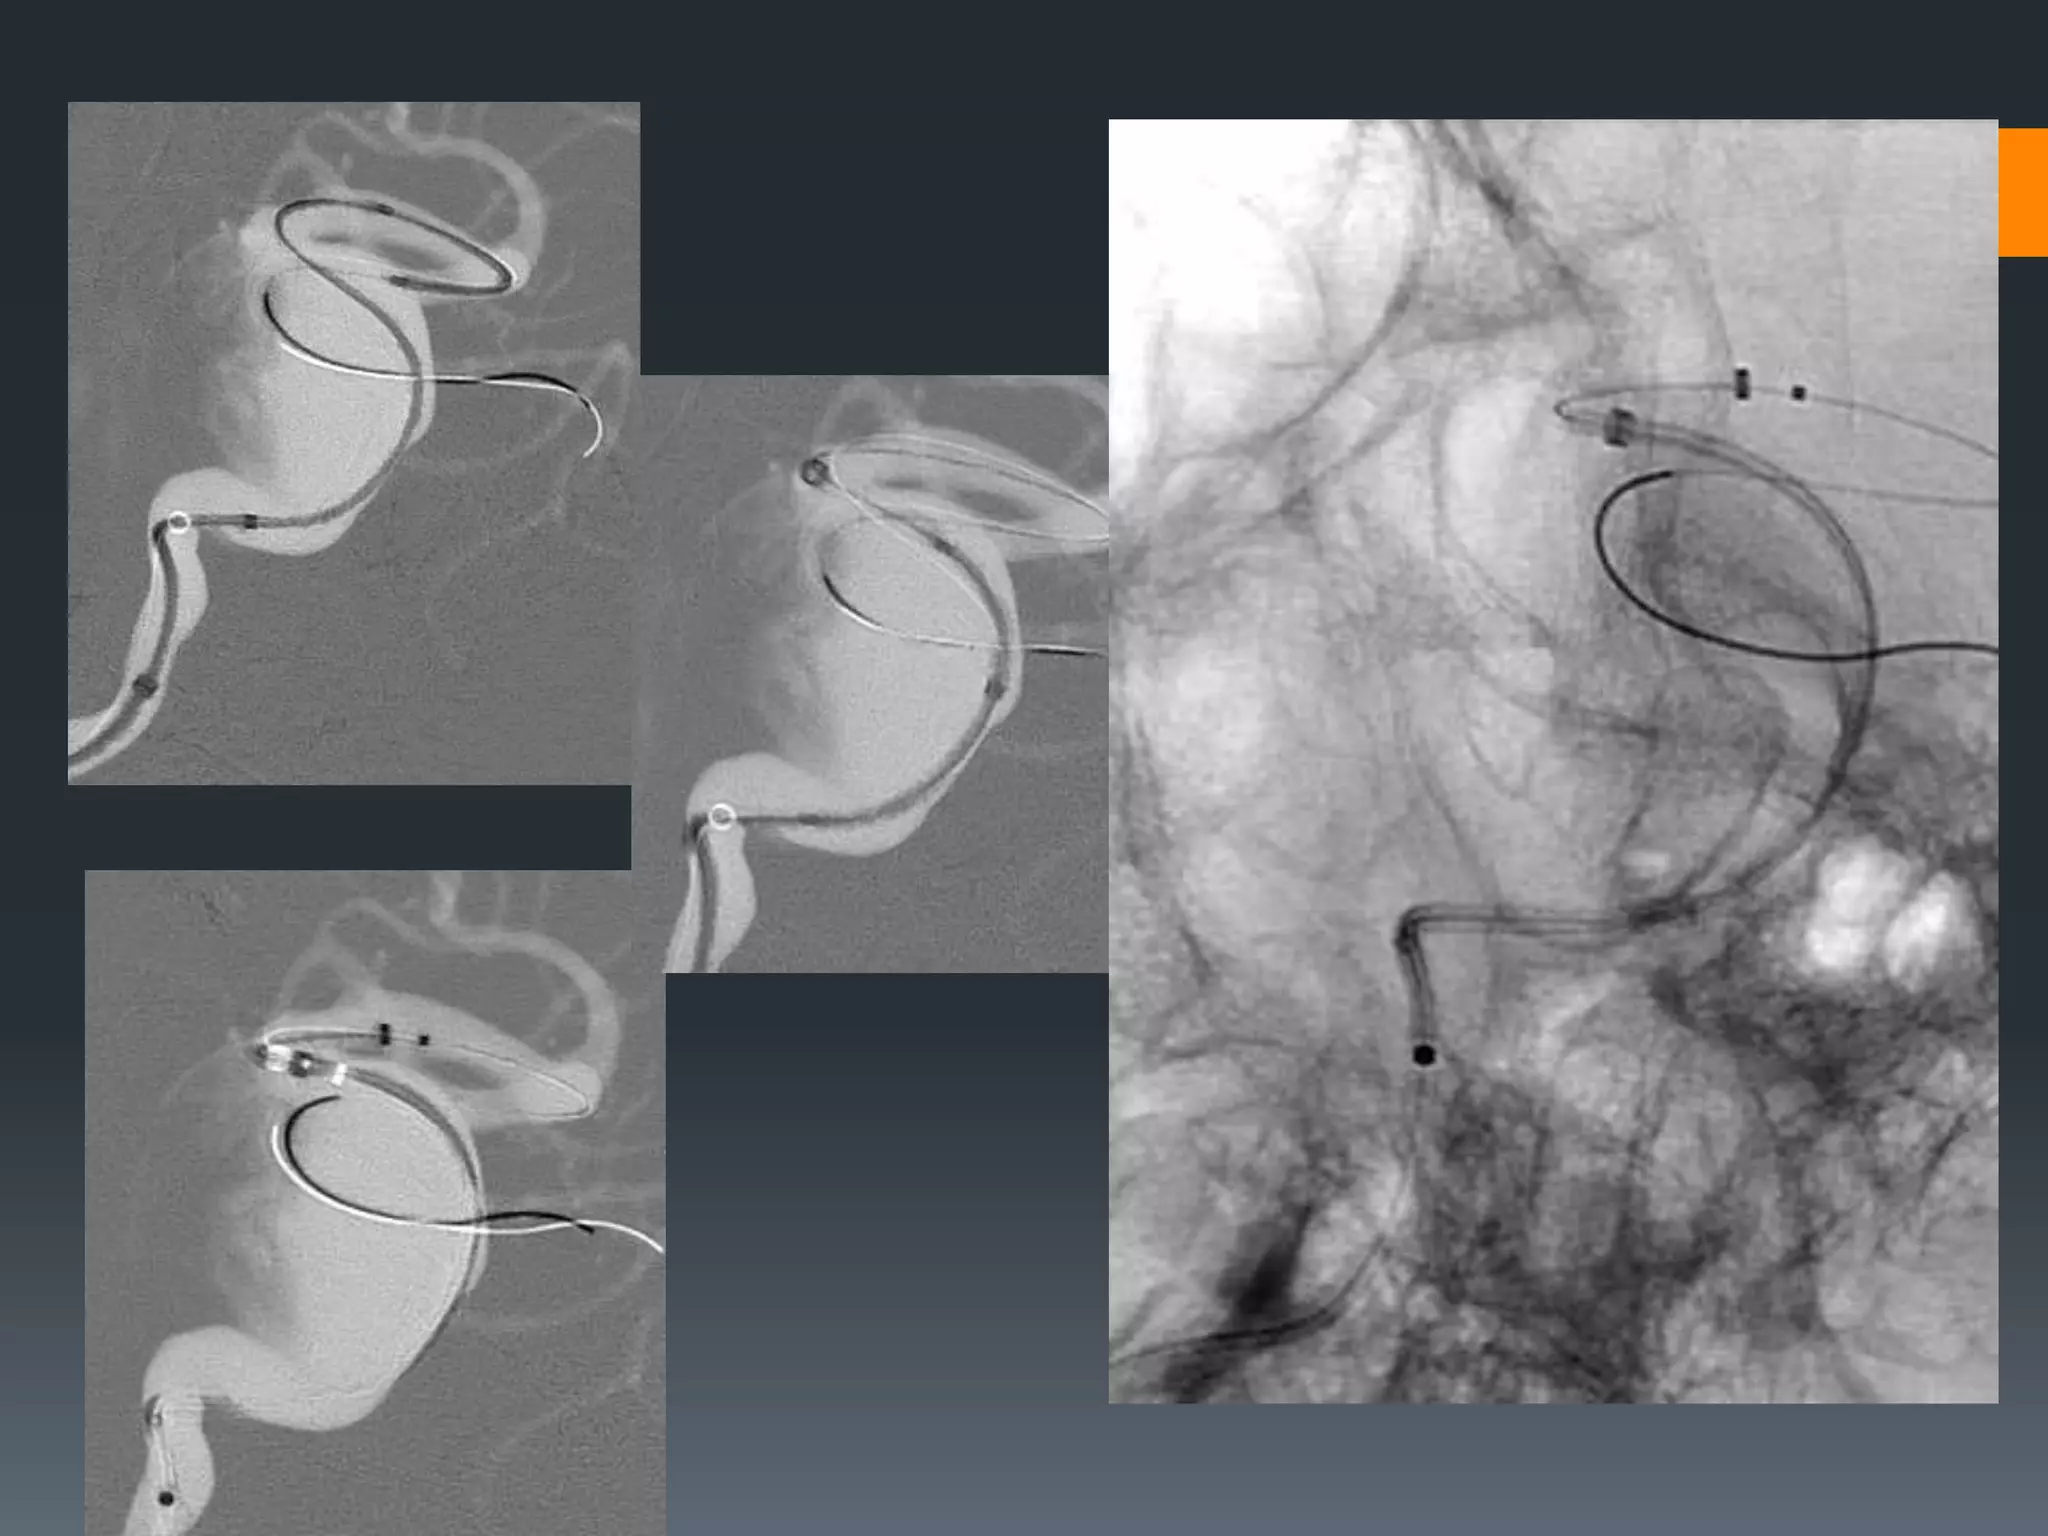

This document discusses tricks and techniques for difficult cannulations during neurointerventional procedures. It outlines strategies for accessing the aortic arch, internal carotid artery (ICA), and areas distal to aneurysms. Long sheaths, distal access catheters, and co-axial techniques are presented as options that have improved cannulation success. Guidance on sheath and catheter selection is provided for different vessel paths. The importance of catheter placement as high as possible in the ICA is emphasized. Reverse curve cannulations are also mentioned. Overall, the document stresses that careful cannulation is critical for procedural success and different strategies may be needed depending on the vessel target.